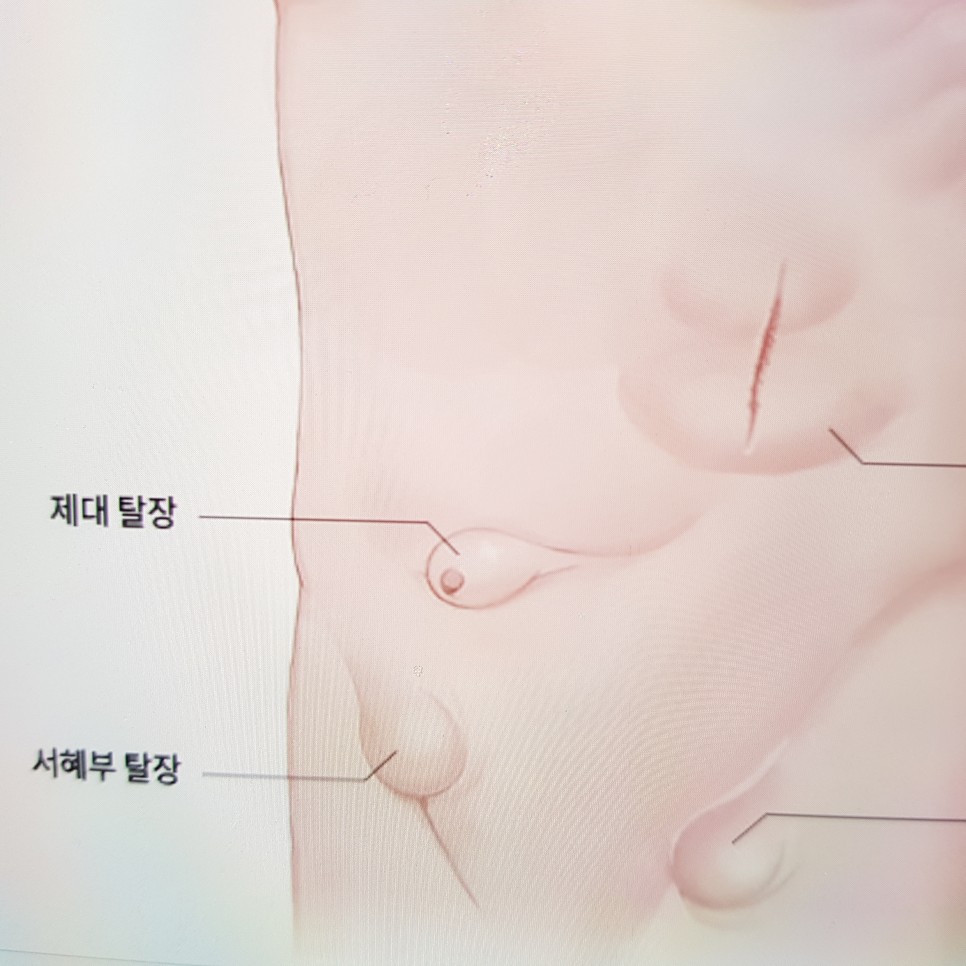

상처 부위, 수술 부위에서 튀어나온 경우 절개 탈장, 배꼽 부분에서 튀어나왔을 경우 배꼽 탈장, 가장 많이 발생하는 탈장이 서혜부에서 발생하는 서혜부 탈장입니다.

서혜부, 즉 사타구니 부분에 디스크가 일어나고 있는 증상인데, 디스크 중 가장 비중이 높습니다. 고환이 나오는 길은 여성보다 남성에게 더 많이 발생하는 것으로 알려져 있습니다.